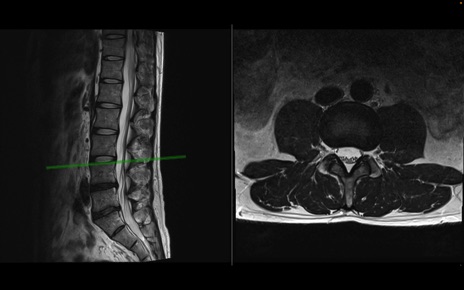

【整形】TIPS症例1 腰椎MRI 横断像と矢状断像

【症例】40歳代男性

【主訴】左臀部〜大腿後面痛み

【現病歴】2週間前から腰痛あり。2日前に夜中にくしゃみをした際に激痛が出現。疼痛強いため来院。

【身体所見】左臀部〜大腿後面、下腿後面のしびれ。SLR -/+ 30度、うつ伏せ困難、筋力低下なし。

異常所見と診断は?